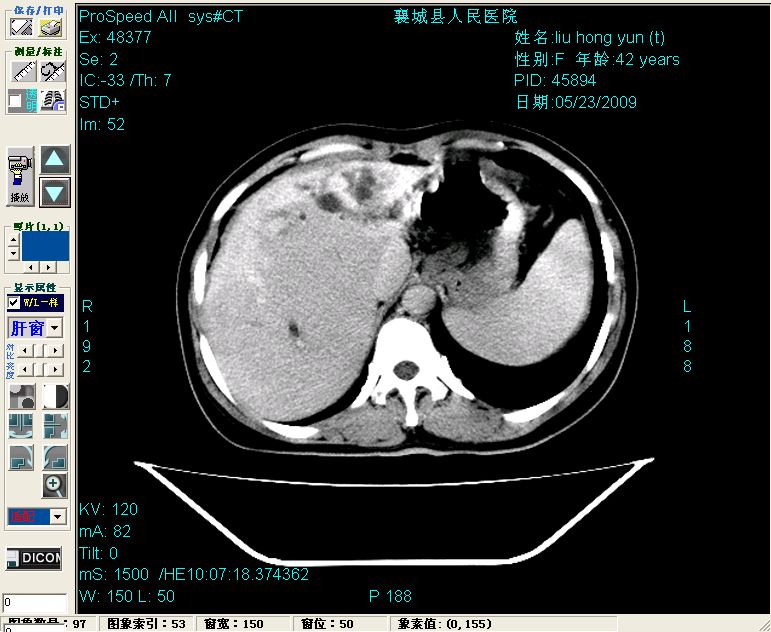

平扫:

平扫左肝外叶体积显著减小,左肝外叶见多房囊性低密度区,左肝实质及右肝前叶浅表实质呈低密度改变,左肝及右肝前叶胆管扩张,脾大

增强动脉期前述低密度区轻度早其强化,门脉期强化程度显著增高,延期扫描强化程度下降,但仍为相对高密度影

2左肝及右肝前叶表现考虑胆囊摘除术后所致的肝动门脉瘘形成,慢性纤维组织炎性增生.不完全除外左肝胆管细胞癌

3脾大,可能与动门脉瘘所致门脉高压有关